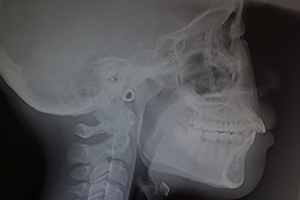

2.セファロ分析

セファロ分析は、頭部の規格化されたレントゲン写真(セファロ)を使って、顎や歯の骨格の位置関係を詳細に解析する方法です。お子さまの成長の状態や不正咬合の程度を客観的に把握でき、適切な治療計画を立てる際に欠かせません。定期的に撮影して比較することで、治療の進行状況や成長の変化も確認でき、安全かつ正確な矯正治療をサポートします。